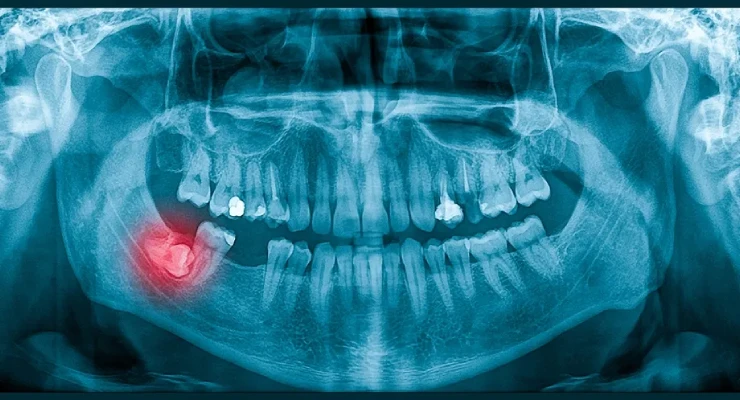

يمكن بسهولة أن تنطمر أضراس العقل في الفك، وعندما يحدث ذلك فإنها تحتاج إلى خلعها جراحيًا. والخبر السار هو أن هذا إجراء شائع يتم إجراؤه عادةً في عيادة الأسنان. في كثير من الحالات، تتم إزالة ضرس العقل بسرعة وسهولة، ولكن في الحالات الأكثر تعقيدًا، قد تتضمن إزالة ضرس العقل قطع كل من اللثة والعظم، وغالبًا ما يلزم إزالة الضرس نفسه إلى أقسام.